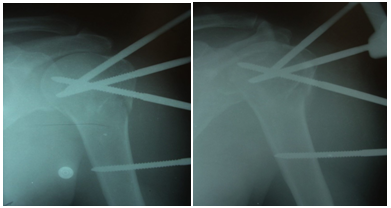

Figure 1 Pre-operative.

Figure 2 Immediate post-operative- Since this was initial of our patients, the greater tuberosity was not considered for fixation; however in our later cases, greater tuberosity was fixed as a rule.

Figure 3 6 Weeks post operative-Prior to fixator removal.

Figure 4 6 months postoperative film-The humeral head appears contained in glenoid and the patient had reasonable shoulder function. The head of humerus did not appear avascular at 6 months.

Figure 5 14 months postoperative-The humeral head appeared contained with post traumatic arthritis due to avascular necrosis. Active abduction was about 90 degrees at shoulder.